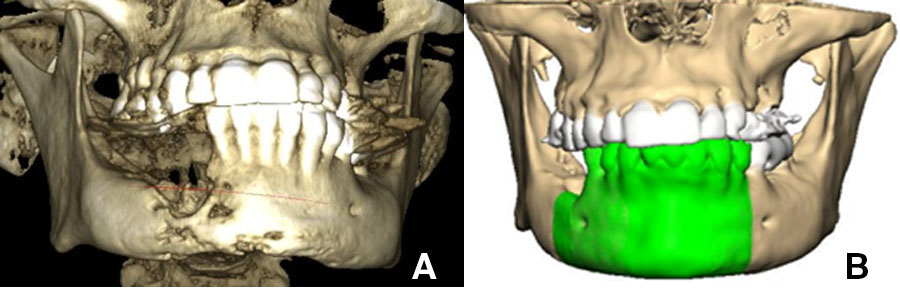

In contrast the particulate, compressed, autologous bone graft overcomes many of these challenges. Due to its mouldable properties it adapts to an arch and allows for the superior restitution of mandibular arch form and alveolar height (Figure 1), whilst significantly reducing patient morbidity and treatment costs.

Images of 3D CBCT scan of patient with advanced osteomyelitis of the mandible (A). Virtual planning (B) is required to produce either a pre-bent or milled patient matched plate.